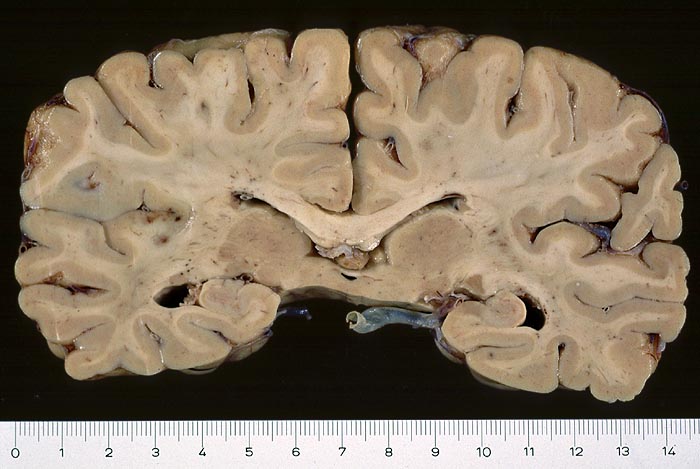

PathoPic – image database / PathoPic ID 2943 - Septikopyämische Herde in der linken Inselrinde

Septikopyämische Herde in der linken Inselrinde

Entzündung infektiös

Hirn parietal

Nervensystem

Endokarditis

Makroskopie